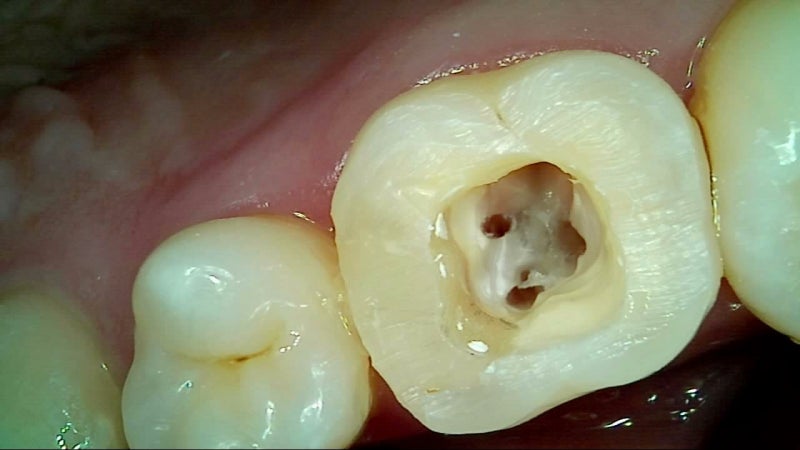

4. 치과 치료 절차 및 소요 비용

치과 치료 절차

- X‑ray 및 육안 진단 → 상태 확인

- 재접착 가능 시 임시/영구 접착 → 안 되면 새 크라운 제작

- 임시 크라운 장착 후 최종 크라운 장착 (1~2주 소요)

- 시술 후 교정력 조정 및 관리법 안내